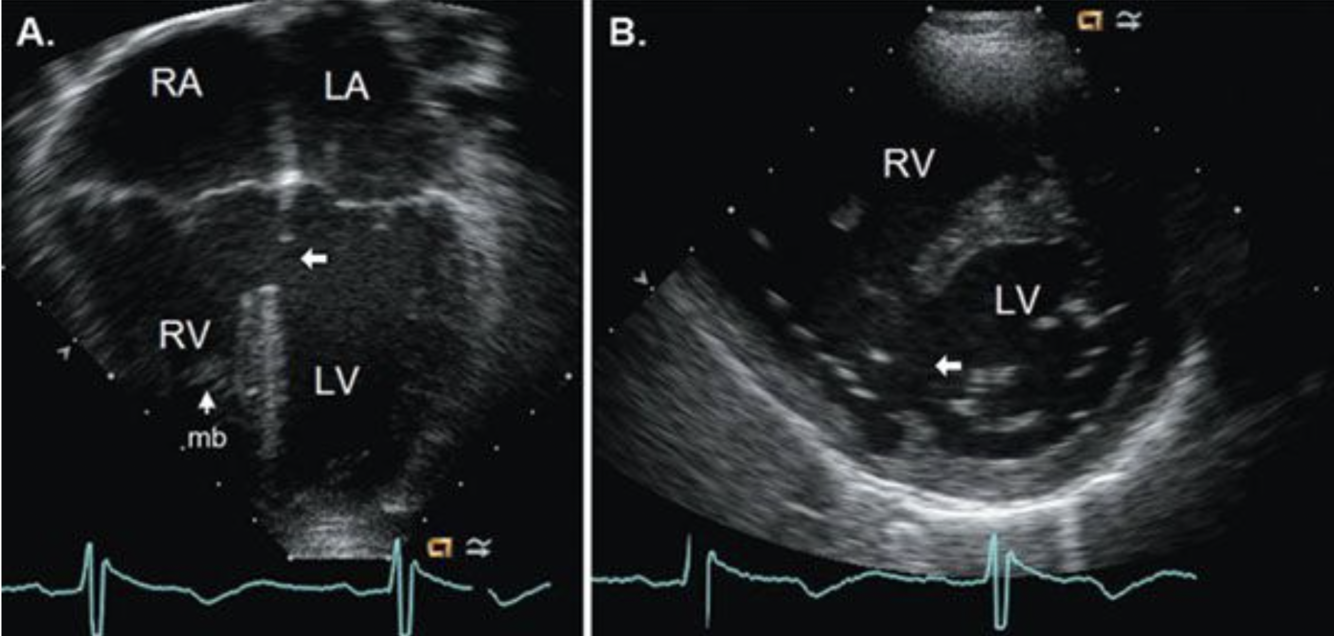

15

Q

What is this (be specific) ?

A

Peri-membranous VSD

16

What is this? (Be specific)

Perimembranous VSD